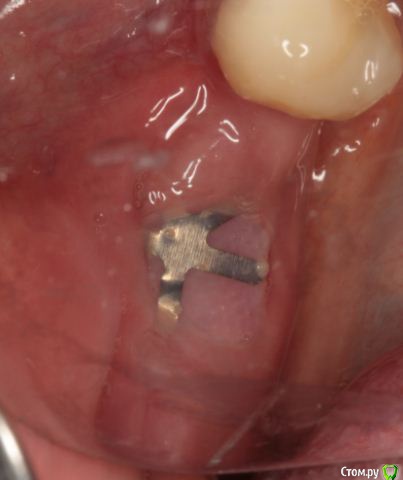

Endorphin Опубликовано 11 августа, 2015 Поделиться Опубликовано 11 августа, 2015 Добрый день, Коллеги!Хочу с Вашей помощью принять оптимальное решение по выходу из сложившейся ситуации.23.06.2015 пациентке проведена аугментация в 4 сегменте. Biooss L+ауто 50:50. Графт перекрыт мембраной biotec с титановым усилением, мембрана перекрыта отжатыми сгустками prp. Ушивание без натяжения (турбомобилизировал по Mane), матрацный и обвивной шов. 27.06 - швы состоятельны, без особенностей04.07 - снятие швов08.07 - при осмотре обратил внимание на незначительный участок оголения мембраны язычно(на фото)решил наблюдать, в надежде что затянется.Пациентка пропала на месяц.11.8.15 - Жалоб нет. Признаков воспаления нет. Обширное оголение мембраны (примерно 1 см2).Принял решение мембрану завтра удалить. Из своих косяков могу выделить слишком дистальное расположение мембраны.Причины неприятности думаю кроются в мембране - у коллеги она очень нередко ведет себя так же. На ощупь она как полиэтилен и, в отличие от cytoplast и goretex (если не ошибаюсь) не имеет пор и полностью изолирует слизистую от кости. Вопрос - как быть с дефектом мягких тканей? Из вариантов - попытаться ушить наглухо или сделать каппу (или защитную пластинку, как в кейсе Большого Зеленого) с пространством для роста грануляций. Склоняюсь ко второму варианту. Буду признателен за любые комментарии. 1 Ссылка на комментарий

Чертков Александр Опубликовано 11 августа, 2015 Поделиться Опубликовано 11 августа, 2015 Только что на осмотре был похожий пациент от коллеги. onemore.JPGНу тут явная "недомобилизация" и неадекватное ушивание. 1 Ссылка на комментарий

Endorphin Опубликовано 9 сентября, 2015 Автор Поделиться Опубликовано 9 сентября, 2015 (изменено) Продолжение истории.По Вашим советам мембрану оставил, наблюдал пациентку раз в неделю. Отмечалась тенденция к росту области прорезывания, в связи с чем было решено мембрану удалить ( не хотелось дожидаться оголения края мембраны). На момент удаления мембране исполнилось 3 месяца. Анестезия, разрез по гребню примерно на 3/4 длины мембраны. Мембрана и пины ушли без боя, в области прорезывания обнаружился желеобразнный фибрин. Там, где над мембраной сохранилась слизистая, на месте графта образовалась твердая ткань, надо полагать, выросла кость. Иммобилизировать, ушивать наглухо, подкладывать сст не стал. Наложил сближающие швы, швы на разрез. Прошла неделя. Через 1.5 - 2 месяца планирую КТ и если это действительно была кость, то имплантацию с сст. Спасибо всем, кто отговаривал меня удалять мембрану . Изменено 9 сентября, 2015 пользователем Endorphin 13 Ссылка на комментарий